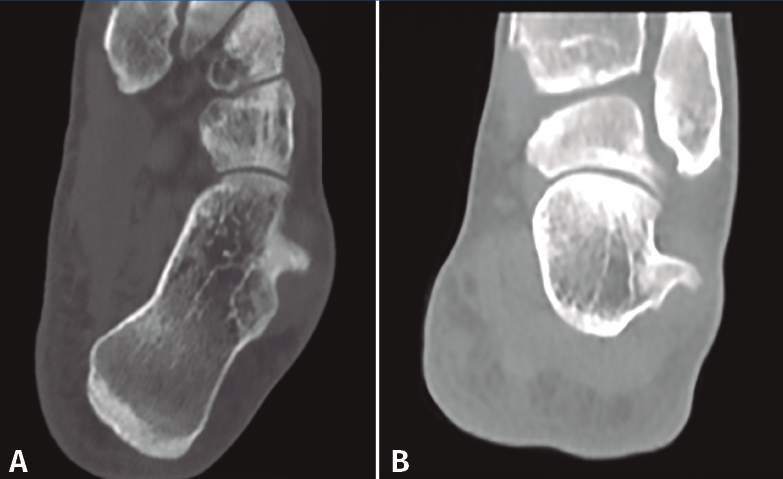

Se realizan los estudios complementarios mediante radiografías, en las que se observa una lesión ósea en la cara lateral del calcáneo con bordes irregulares (Figura 2). La resonancia magnética nuclear informa de “hipertrofia del tubérculo lateral del calcáneo que conlleva severa afectación de los tendones peroneos apreciando signos de tenosinovitis y afectación mayor del tendón peroneo lateral largo con rotura parcial del mismo” (Figuras 3A y 3B). La tomografía computarizada muestra una “exóstosis en cara externa de calcáneo de 12 × 9 × 8 mm” (Figuras 4A y 4B).

Figura 4. Imágenes de tomografía axial computarizada donde se ve la tumoración de 12 × 9 × 8 mm.